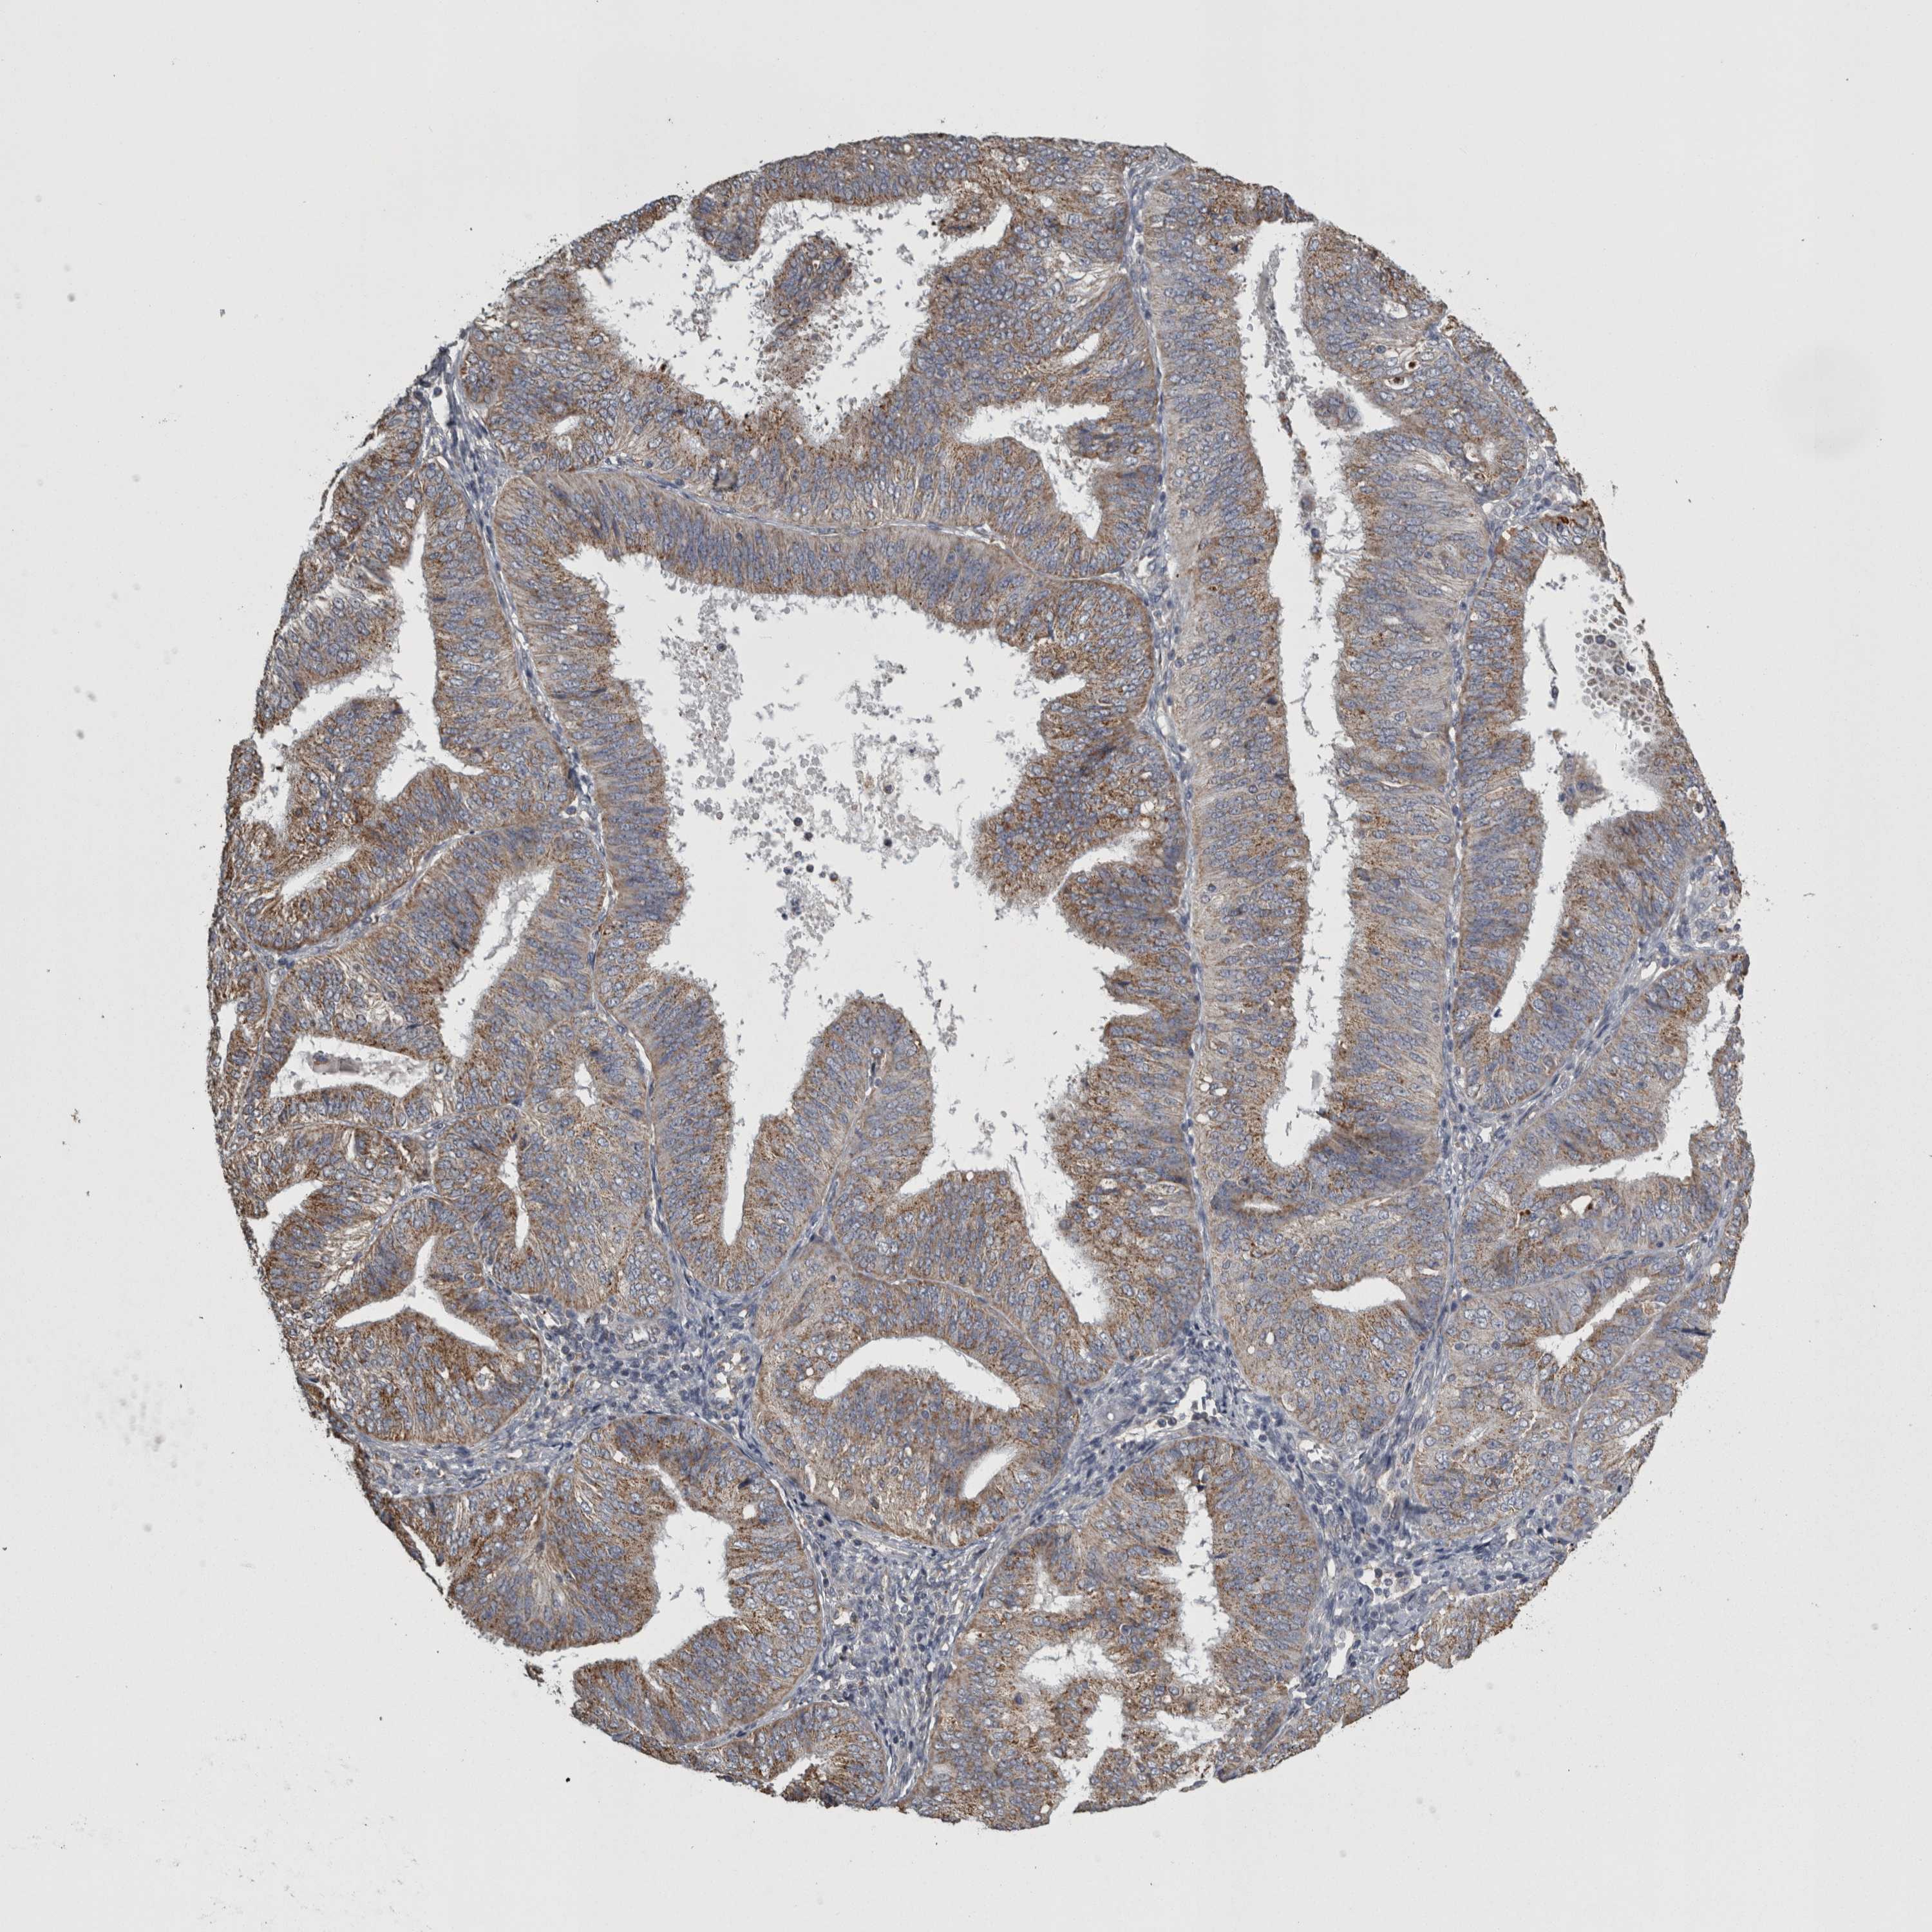

ENDOMETRIAL CANCER - Protein expressioni

A mouse-over function shows sample information and annotation data. Click on an image to view it in a full screen mode. Samples can be filtered based on level of antibody staining by selecting one or several of the following categories: high, medium, low and not detected. The assay and annotation is described here.

Note that samples used for immunohistochemistry by the Human Protein Atlas do not correspond to samples in the TCGA dataset.

Antibody stainingi

Antibody staining in the annotated cell types in the current human tissue is reported as not detected, low, medium, or high, based on conventional immunohistochemistry profiling in selected tissues. This score is based on the combination of the staining intensity and fraction of stained cells.

Each image is clickable and will lead to virtual microscopy that enables deeper exploration of all samples and also displays staining intensity scores, fraction scores and subcellular localization as well as patient and tissue information for each sample.

Antibody HPA072590

Antibody CAB025217

Staining

High

Medium

Low

Not detected

Intensity

Strong

Moderate

Weak

Negative

Quantity

>75%

75%-25%

<25%

None

Location

Nuclear

Cytoplasmic/membranous

Cytoplasmic/membranous,nuclear

Adenocarcinoma, NOS